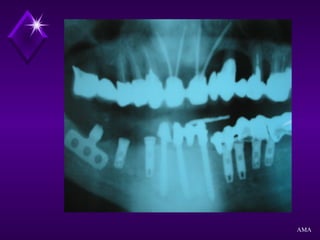

EXAME RADIOGRÁFICO

Radiografias Periapicais

Radiografia Panorâmica

Radiografia de Perfil

Planigrafias

Tomografia Computadorizada

AMA